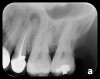

There are two specific types of DIDR sensor systems available to dentists in the marketplace: the hard-wired (HW) sensor and the photostimulable phosphor (PSP) sensor,1,2 also commonly known as phosphor "plates." A desirable feature common to both modalities is the ability to expose either bitewing (BW) or PA radiographic images. The BW radiograph (Figure 1) is usually considered more appropriate for caries detection, whereas the PA (Figure 2) is diagnostic for several different anatomic and pathologic issues.7

Fig 1. Left: Representative PSP BW radiograph with multiple restorative materials of varying radiographic densities. Tooth No. 31 demonstrates deep

caries on mesial aspect beneath the restorative. Radiolucency of carious lesion results from the low relative density of caries compared with healthy

tooth structure. Right: PSP BW radiograph optimized for view of multiple interproximal carious lesions.

Figure 1